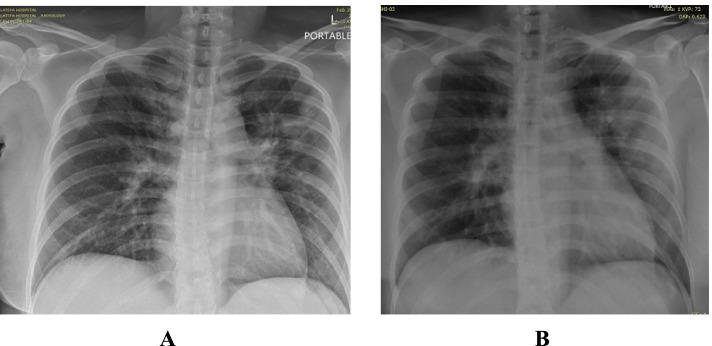

This is a retrospective case series study. We have included seven pregnant women admitted with early COVID-19 infection to a tertiary care hospital, Latifa Maternity Hospital in Dubai, United Arab Emirates between 12 February and 04 March 2021 and who consented to receive COVID-19 convalescent plasma as part of their treatment plan. Main outcomes measured were clinical and radiological features, laboratory tests, WHO clinical progression scale pre and post treatment, and maternal, fetal outcomes. COVID-19 clinical severity was classified according to the NIH guidelines for criteria of SARS-CoV-2. For the radiological features, a modified chest X-ray scoring system was used where each lung was divided into 6 zones (3 on each side upper, middle, and lower). Opacities were classified into reticular, ground glass, patchy and dense consolidations patterns.

这是一项回顾性病例系列研究。我们纳入了 2021 年 2 月 12 日至 3 月 4 日期间在阿拉伯联合酋长国迪拜拉蒂法妇产医院因早期 COVID-19 感染住院且同意接受 COVID-19 恢复期血浆治疗的 7 名孕妇。主要观察指标为临床和影像学特征、实验室检查、治疗前后世界卫生组织临床进展量表(WHO 临床进展量表)以及母婴结局。根据 NIH 指南,COVID-19 临床严重程度分为 SARS-CoV-2 标准。对于影像学特征,使用改良的胸部 X 线评分系统,每个肺分为 6 个区(每侧上、中、下各 3 个区)。将不透明性分为网状、磨玻璃、斑片状和致密性实变。